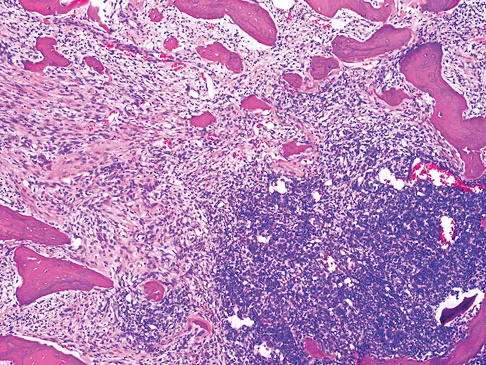

Figures 12a through 12e show the radiograph, MRI scans, and biopsy specimens of a 17-year-old boy. What is the most likely diagnosis?

The images show an epiphyseal lesion. The MRI scan shows extensive bone edema surrounding the lesion, consistent with chondroblastoma. Histology shows polygonal chondroblasts in a cobblestone-like pattern and areas of calcification consistent with chondroblastoma. Although some giant cells are seen, the age of the patient and the polygonal chondroblasts differentiate this lesion from giant cell tumor. Clear cell chondrosarcoma is an epiphyseal lesion that occurs in an older population, and the cells have clear cytoplasm. This lesion is not producing bone on imaging or histologic specimen, eliminating osteosarcoma. Tuberculous septic arthritis can be an epiphyseal lesion, but granulomas would be seen on histology. Menendez LR (ed): Orthopaedic Knowledge Update: Musculoskeletal Tumors. Rosemont, IL, American Academy of Orthopaedic Surgeons, 2002, pp 103-111.